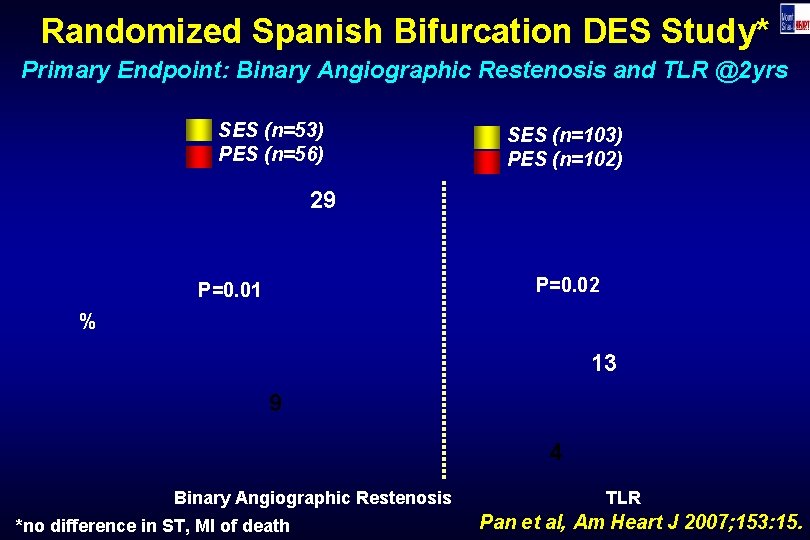

Randomized Spanish Bifurcation DES Study* Primary Endpoint: Binary Angiographic Restenosis and TLR @2 yrs SES (n=53) PES (n=56) SES (n=103) PES (n=102) 29 P=0. 02 P=0. 01 % 13 9 4 Binary Angiographic Restenosis *no difference in ST, MI of death TLR Pan et al, Am Heart J 2007; 153: 15.